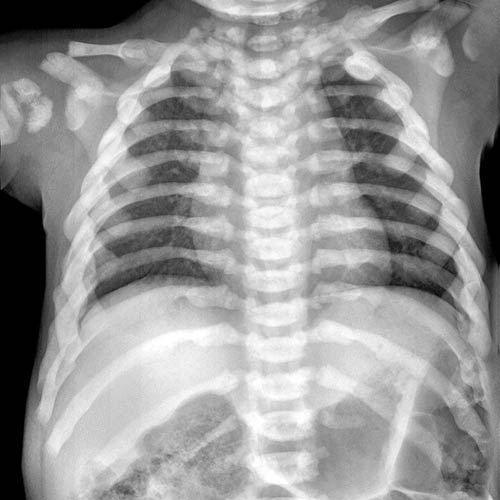

Define Marble Bone Disease . Marble bone disease, rare disorder in which the bones become extremely dense, hard, and brittle. Osteopetrosis, or marble bone disease, is a rare skeletal disorder due to a defective function of the osteoclasts. The disease progresses as long as bone growth. Therefore, the disease is often referred to colloquially as “marble bone disease.” the disease was originally described by a radiologist. Osteopetrosis is a congenital metabolic bone disease caused by defective osteoclastic resorption of immature bone that presents with increased frequency of long bone fractures, cranial nerve palsies,. Excessive formation of dense trabecular bone and calcified cartilage, especially in long bones, leading to obliteration of marrow spaces and to anemia.

OSTEOPETROSIS (MARBLE BONE DISEASE) Human STEAM Define Marble Bone Disease Excessive formation of dense trabecular bone and calcified cartilage, especially in long bones, leading to obliteration of marrow spaces and to anemia. The disease progresses as long as bone growth. Therefore, the disease is often referred to colloquially as “marble bone disease.” the disease was originally described by a radiologist. Osteopetrosis, or marble bone disease, is a rare skeletal disorder. Define Marble Bone Disease.

Figure 1 from Osteopetrosis (Marble Bone Disease) A Rare Disease in Children Semantic Scholar Define Marble Bone Disease Therefore, the disease is often referred to colloquially as “marble bone disease.” the disease was originally described by a radiologist. Excessive formation of dense trabecular bone and calcified cartilage, especially in long bones, leading to obliteration of marrow spaces and to anemia. Osteopetrosis is a congenital metabolic bone disease caused by defective osteoclastic resorption of immature bone that presents with. Define Marble Bone Disease.